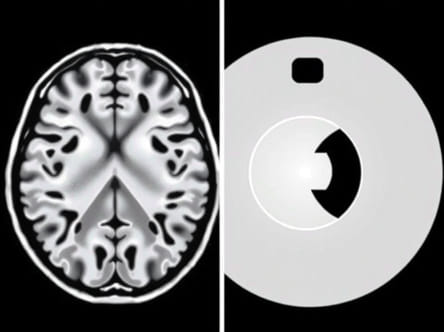

Magnetic Resonance Imaging, or MRI, is an advanced imaging technique that uses strong magnetic fields and radio waves to produce detailed images of the internal structures of the body. Unlike X-rays or CT scans, MRI does not involve ionizing radiation, making it a safer option for repeated imaging when necessary. MRI is particularly effective for soft tissue imaging, such as the brain, spinal cord, muscles, ligaments, and organs. By providing high-resolution images, MRI allows for the detection of subtle abnormalities that might not be visible with other imaging methods.

MRI technology relies on the principles of nuclear magnetic resonance. When a patient is placed in a strong magnetic field, the protons in the body’s hydrogen atoms align with the field. Radiofrequency pulses are then applied, causing these protons to emit signals as they return to their original alignment. These signals are captured by the MRI machine and processed by a computer to create detailed images of the body’s internal structures. Different tissues produce varying signal intensities, which allows MRI to distinguish between normal and abnormal tissue.

Computed Tomography, commonly known as a CT scan, is an imaging technique that combines multiple X-ray measurements taken from different angles to create cross-sectional images of the body. CT scans are highly effective for visualizing bones, detecting internal bleeding, and identifying lung, chest, and abdominal conditions. The rapid imaging process makes CT scans particularly useful in emergency situations, where speed and accuracy are critical for diagnosis and treatment.

CT scanners use a rotating X-ray device that captures multiple images of the body in thin slices. These images are then processed by a computer to generate detailed cross-sectional views, which can be further reconstructed into three-dimensional images. CT imaging relies on the absorption of X-rays by different tissues dense structures like bones absorb more radiation and appear white, while softer tissues absorb less and appear in shades of gray. This differential absorption allows CT scans to distinguish between various tissues and detect abnormalities.

• MRI excels in soft tissue contrast, making it ideal for brain, muscle, ligament, and organ imaging.

• CT is superior for imaging bones, detecting fractures, and identifying acute bleeding.